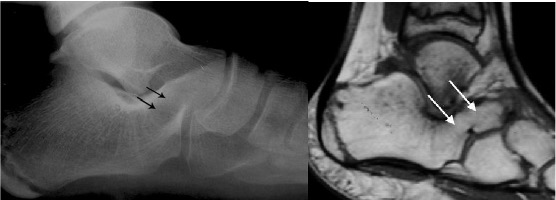

Talo-calcaneal coalition

- Occurs on the medial side of the talus

- Usually at the middle subtalar facet

- Prominent talar beak arising from dorsal talar head or neck (not obvious in this image)

- C sign – Formed by prominence of inferior border of sustentaculum and talar dome on lateral projection (NB this is not diagnostic of coalition as it can often be seen with a valgus heel e.g. flat foot)

Talocalcaneal coalition with characteristic C shape (arrows) on lateral view